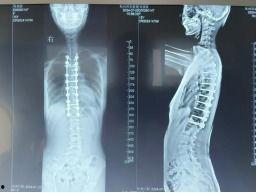

手术开始了,医生首先在女孩的背部切开一个小口,然后插入一根细长的金属棒。这根金属棒将贯穿整个脊柱,起到支撑和矫正的作用。接下来,医生在金属棒的两侧分别安装了两个金属钩,将它们固定在女孩的脊椎骨上。

随后,医生开始调整金属钩的位置,使脊柱恢复到正常状态。这一过程需要精确的操作,因为任何一点偏差都可能导致手术失败。经过一番努力,医生终于将脊柱矫正到理想的位置。

接下来,医生将金属棒与金属钩连接起来,形成一个稳定的支架。医生在手术切口处缝合,手术宣告成功。